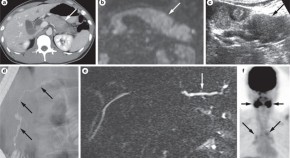

Autoimmune pancreatitis (AIP) is a unique form of pancreatitis that is suspected to involve autoimmune mechanisms. Given that AIP responds dramatically to steroid therapy, it is important to distinguish it from pancreatic cancer. AIP may be one manifestation of IgG4-related sclerosing disease, which is a systemic disease in which IgG4-positive plasma cells and T lymphocytes extensively infiltrate various organs. Kamisawa and colleagues describe the clinical and pathophysiological features of AIP and IgG4-related sclerosing disease.